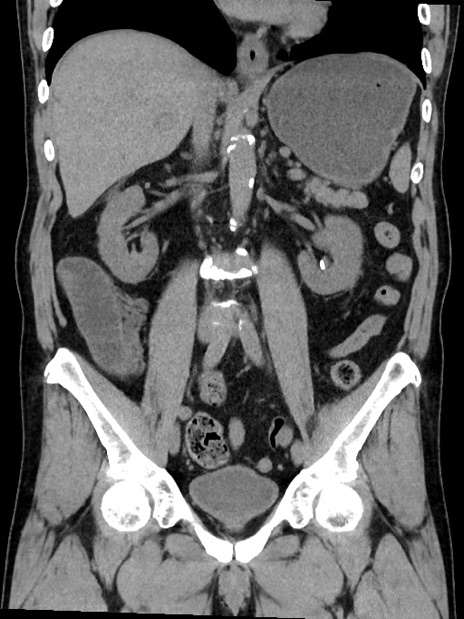

症例35(冠状断像)

【症例】70歳代 男性

【主訴】腹部膨満、嘔吐

【現病歴】昨日より腹部膨満感出現。本日増悪し、仙痛出現。嘔吐あり、受診。

【既往歴】糖尿病、胆摘後

【身体所見】BP 149/80mmHg、HR 74/min、BT 35.9℃、腹部:膨満、軟、圧痛なし。腸雑音減弱あり。上腹部正中切開瘢痕あり。

【データ】WBC 13500、CRP 1.72